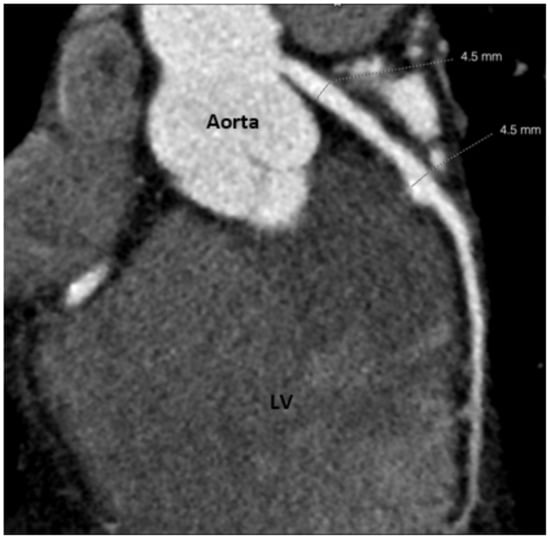

2. Case Report